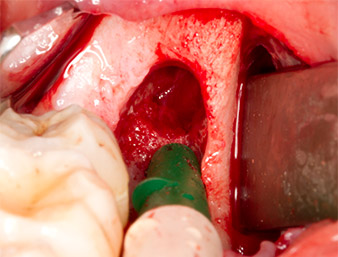

To expose the root remnant with as little trauma as possible to the tissue, a further instrument was used (Piezomed S2) that is primarily indicated for preparing the lateral window in augmentations of the sinus floor. The diamond-coated ball was additionally used to smooth sharp bone edges (Fig. 6 and 7). All the Piezomed attachments were used with the relevant automatic default setting without booster function.

Piezomed S2

Fig. 6: The root remnant is carefully exposed with a diamond-coated spherical instrument (Piezomed S2), bone edges are smoothed.

root remnant 38

Fig. 7: The root remnant 38 (LL8) is well exposed in its alveole for subsequent removal.